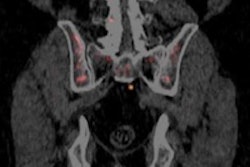

Imaging specialists have a new weapon in their arsenal for diagnosing prostate cancer after the U.S. Food and Drug Administration last week approved a PET radiopharmaceutical from Blue Earth Diagnostics.

Called Axumin, the agent is intended for use in men who are suspected of having recurrent prostate cancer, based on elevated prostate-specific antigen (PSA) levels after primary treatment.

In particular, Axumin is designed for use in men with very low PSA levels whose cancer recurrence might not be detected with other imaging tools. Learn more about Axumin by clicking here.